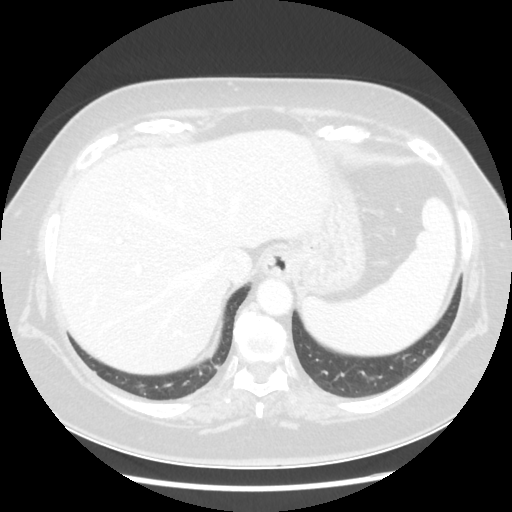

Image Grid

4Γ—3 grid: Rows show different image types (Original NATIVE, Reconstructed NATIVE, Original VENOUS, Generated VENOUS), Columns show windowing techniques (No Window, Lung Window, Mediastinum Window)

Original VENOUS CT scan

No window - Raw intensity values